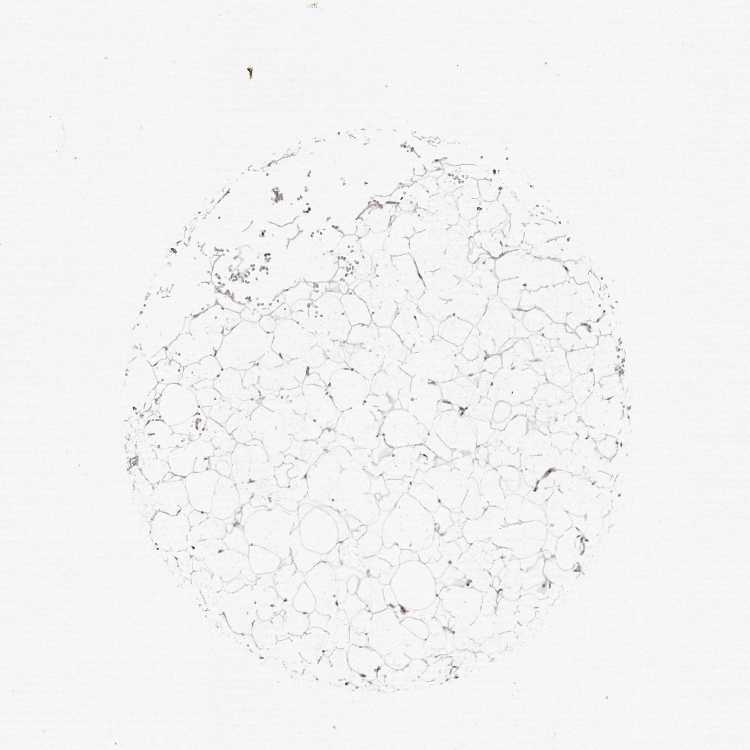

ADIPOSE TISSUE - Antibody stainingi

Antibody staining in the annotated cell types in the current human tissue is reported as not detected, low, medium, or high, based on conventional immunohistochemistry profiling in selected tissues. This score is based on the combination of the staining intensity and fraction of stained cells.

Each image is clickable and will lead to virtual microscopy that enables deeper exploration of all samples and also displays staining intensity scores, fraction scores and subcellular localization as well as patient and tissue information for each sample.

Antibody HPA028325Antibody HPA028435Antibody HPA030097

Adipocytes Not detectedNot detectedNot detected